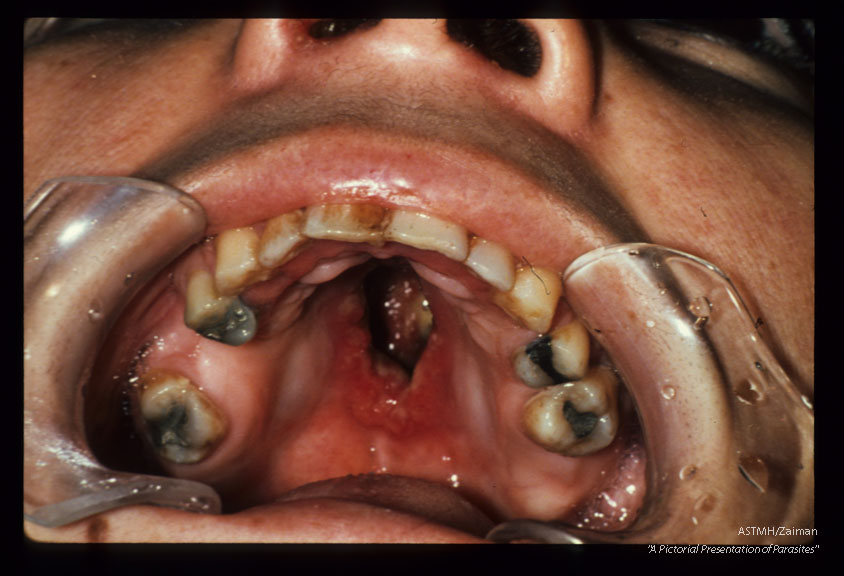

Mucocutaneous (Peru). Destruction of hard palate.

Description: Mucocutaneous (Peru). Destruction of hard palate.